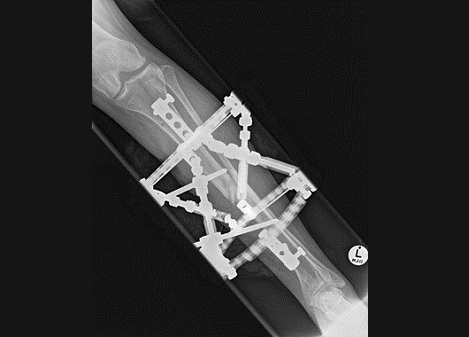

Fig7. - Complex proximal tibia fracture.

Fig7. - Treated with a hexapod type external fixator.